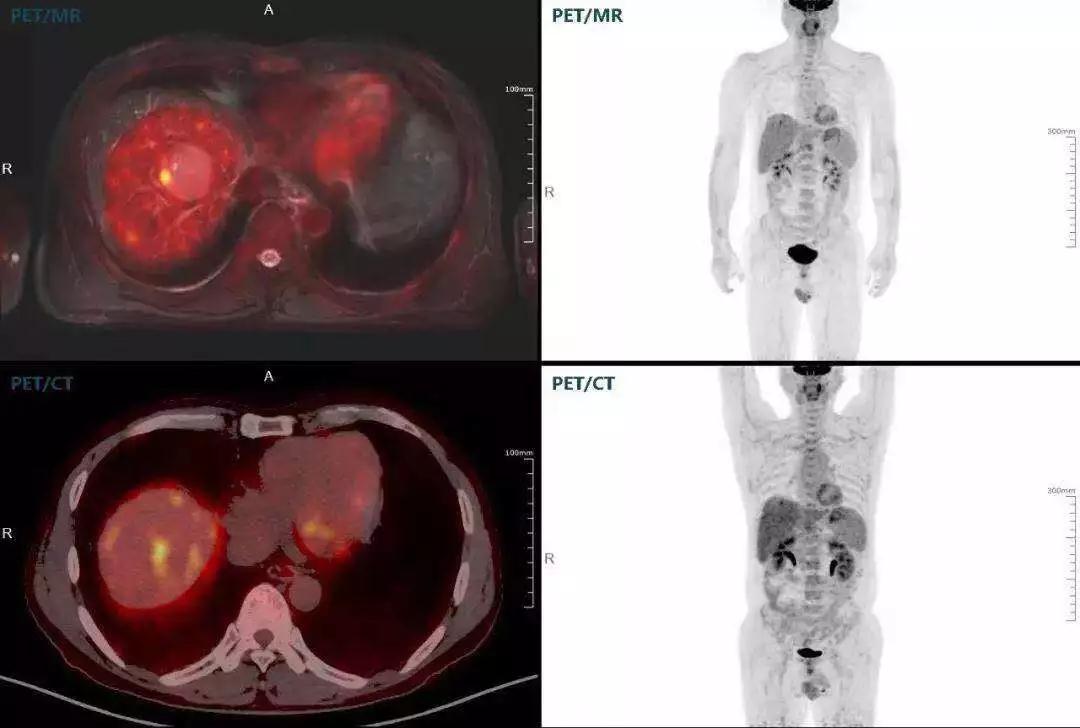

肝癌

聯(lián)影“時(shí)空一體”超清TOF PET/MR搭載的壓縮感知技術(shù),能夠同時(shí)實(shí)現(xiàn)16期成像,精準(zhǔn)捕獲肝臟動(dòng)態(tài)影像的每一瞬間,同時(shí)兼顧早期與晚期等全部期相的完整病灶信息,實(shí)時(shí)、全方位鎖定病灶。同時(shí),基于其2.8mm超高分辨率,能夠精細(xì)呈現(xiàn)腫瘤邊界信息,捕捉局部微小病灶與遠(yuǎn)端轉(zhuǎn)移灶,助力醫(yī)生精準(zhǔn)診斷。

(對于同一例肝臟惡性腫瘤,PET-CT與PET/MR成像對比??梢钥吹?,聯(lián)影PET/MR圖像對腫瘤邊界和FDG高濃聚區(qū)域清晰顯示。)